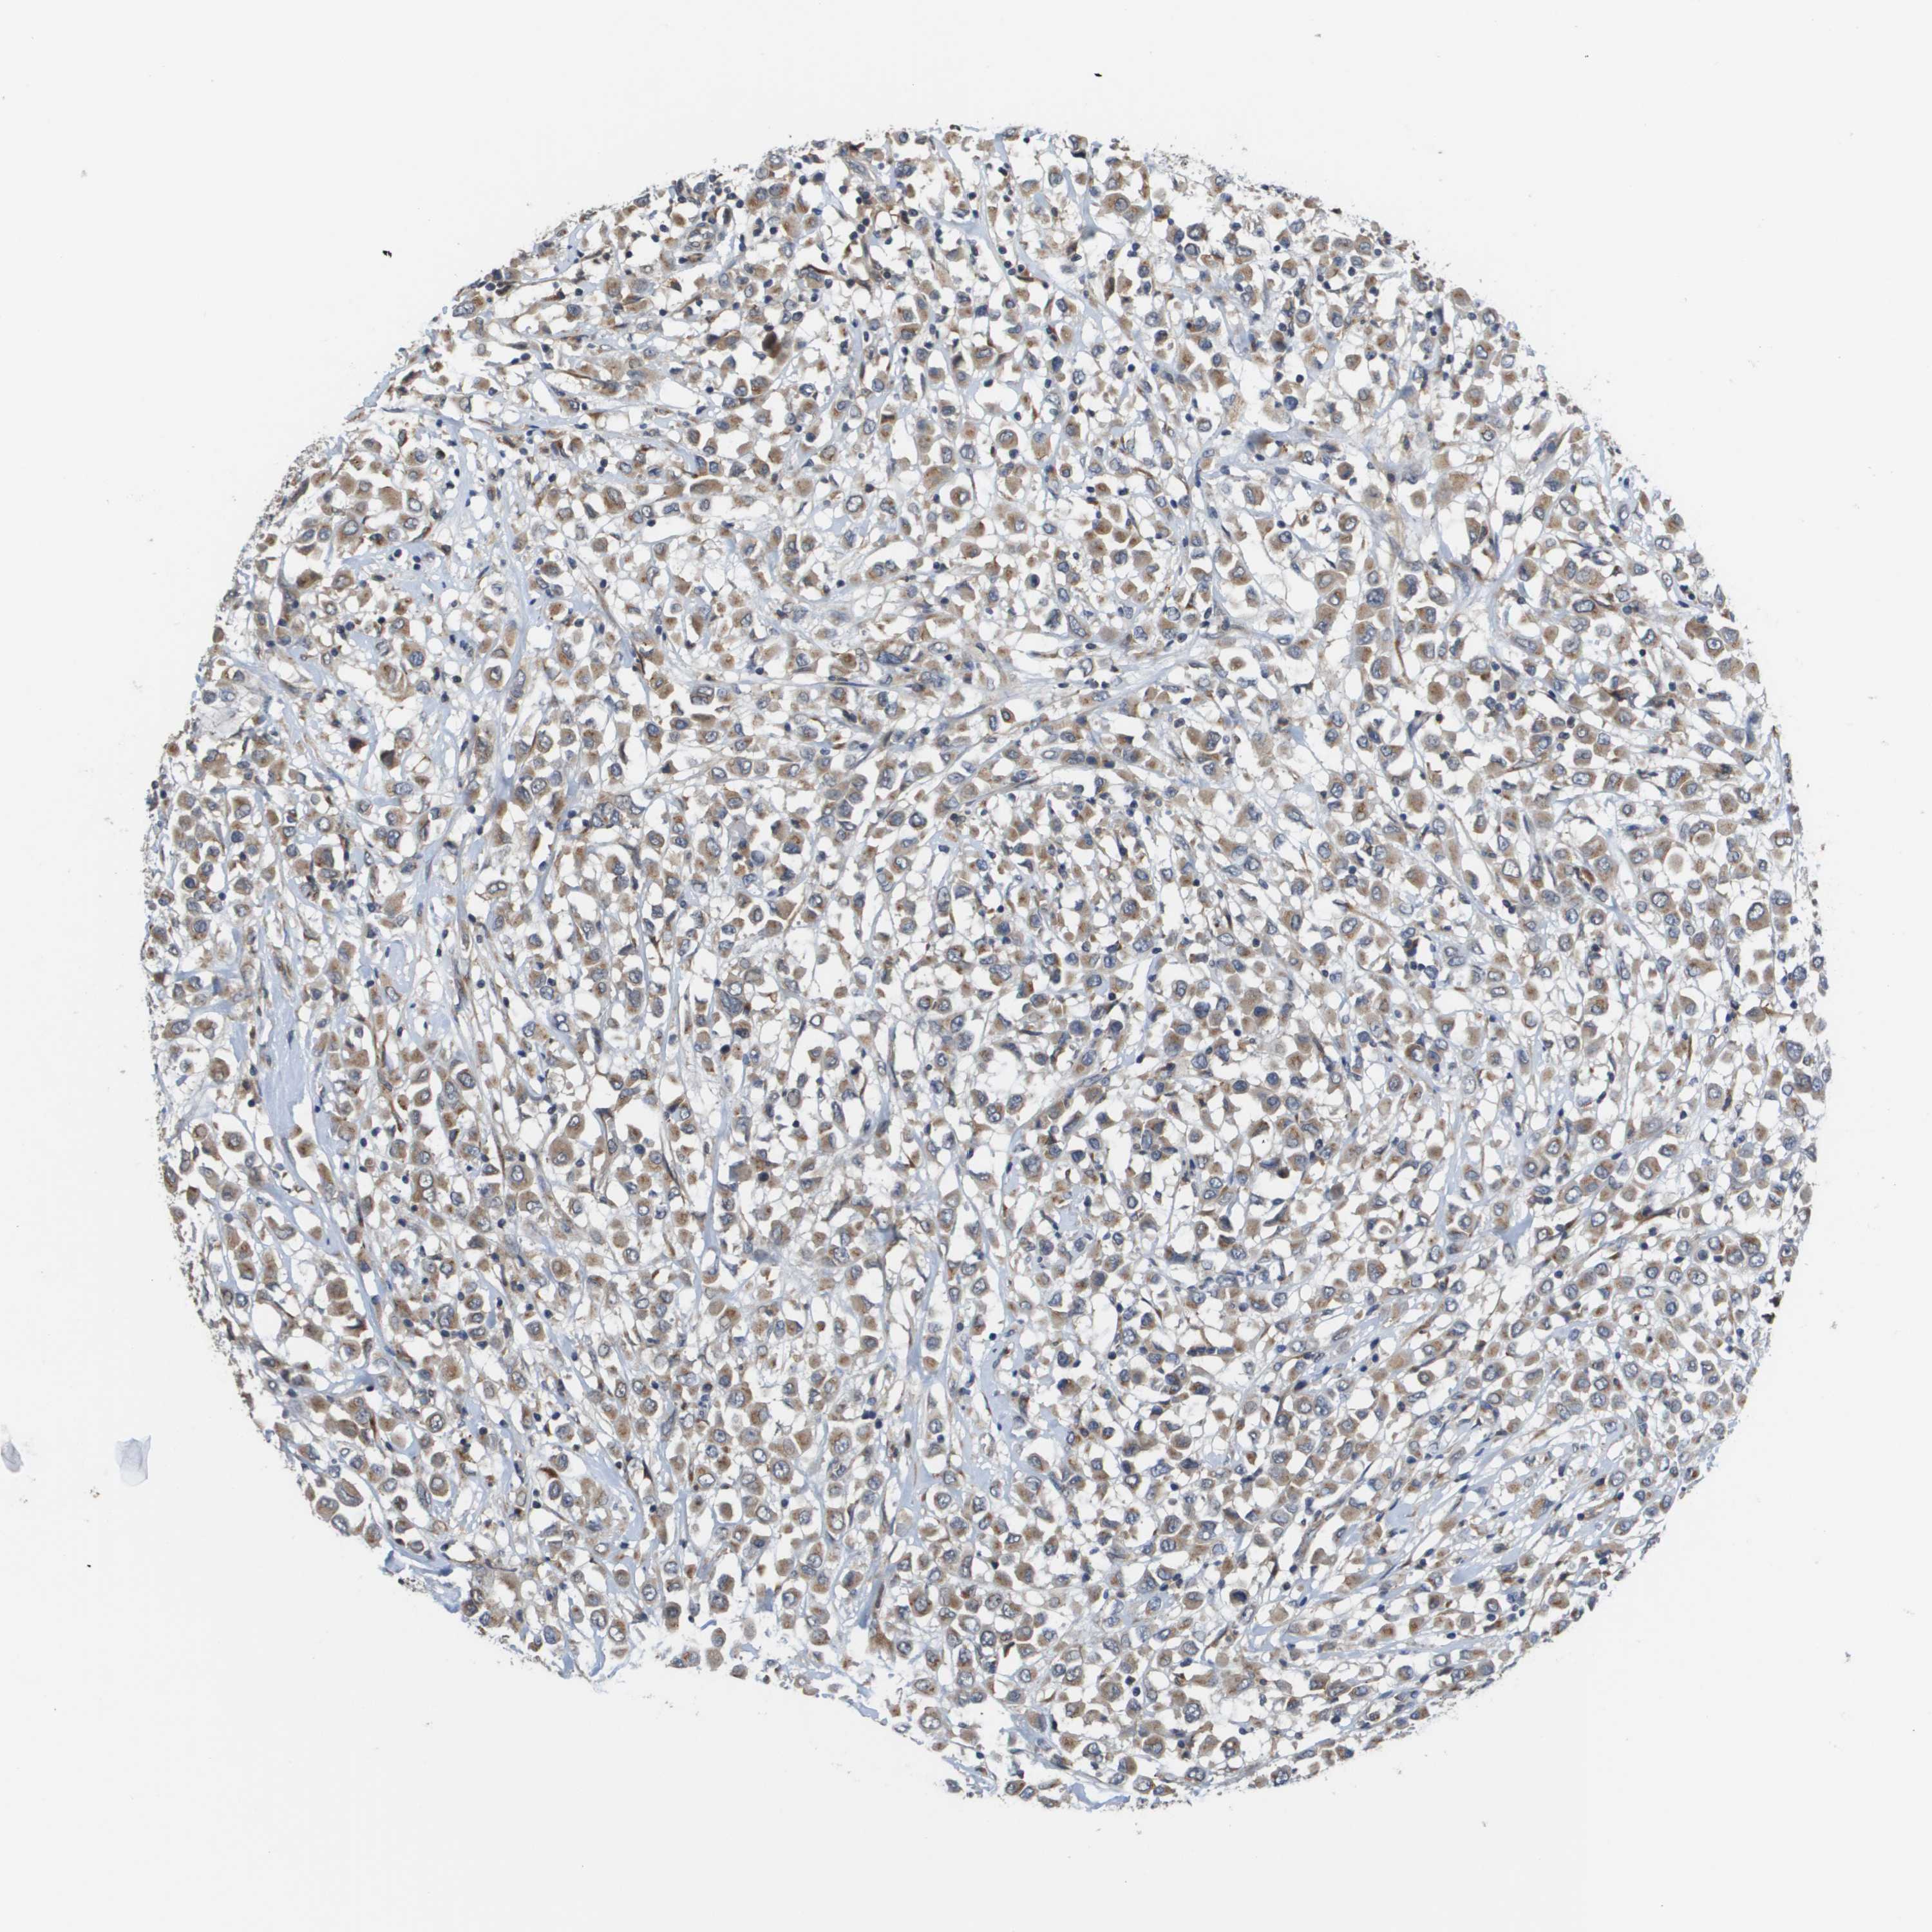

CANCER BREAST CANCER Show tissue menu

BRCA TCGA BRCA VALIDATION PROTEIN EXPRESSION